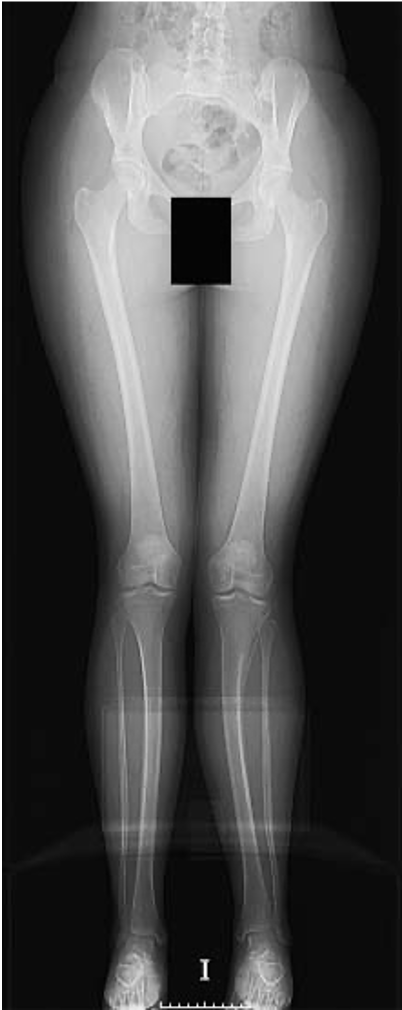

Standing long-films

Parameters;Right;Left;Normal;Discrepancy;Normal discrepancy

Femur anteversion;20°;-6°;20-25°;26°;0-15° Tibiae retroversion;30°;19°;30-35°;11°;0-15°